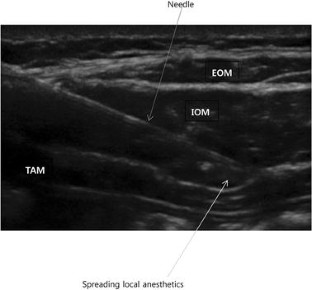

Fig. 1